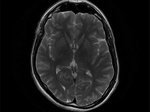

Более того, как показали снимки МРТ в исследованиях, количество ткани сильно зависит от длительности такого заболевания. Так, результаты исследования американских ученых показали, что у пациентов, которые болели сахарным диабетом более 15-ти лет, было намного меньше серого вещества в мозгу, нежели у пациентов, у которых диагноз такой болезни был менее 4-х лет тому назад.

Ранее уже было известно о высоком негативном влиянии этой болезни на мозг человека. Но ранее считали, что причина в сокращении кровотока в мозг, что в свою очередь повышает инсульт. Однако в результате этих последних исследований выяснилось новая угроза для пациентов — мозговая ткань у диабетиков уменьшается в два раза быстрее. Так, если у здоровых с течением времени здоровый человек теряет 2 куб. см. за один год, то у пациентов с таким диагнозом — 4 куб. см. в год.